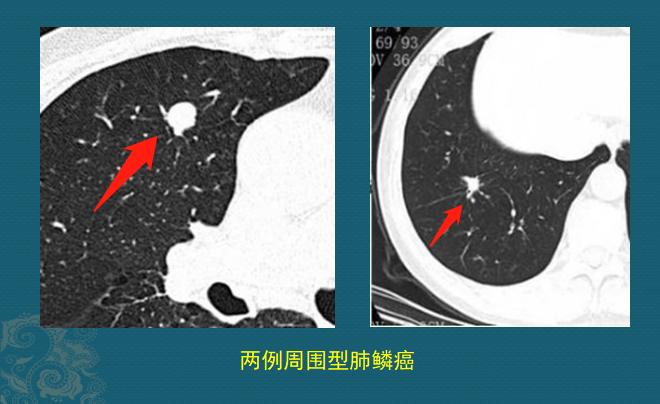

这种的多表现为肺结节,具备恶性征象的大家都会看,比如有分叶、毛刺、偏心小空洞、小气管截断等,我们介绍两个不典型的:光滑小结节、硬结灶。

少部分早期周围型肺鳞癌可以很光滑圆润,没有明显恶性征象,貌似良性肺结节;还有些貌似良性的肺纤维灶,定期复查是很好的鉴别方法:

病例来自浙江舟山曹捍波教授

这两位老爷子都是周围型肺鳞癌,左边这个很光滑,右边这个像硬结灶,随访观察都缓慢长大,排除了陈旧性良性病灶,果断手术切除,治愈了。这么小的肿瘤,早期生长速度都很慢,随访观察不会耽误治疗。